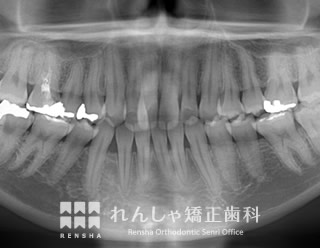

過蓋咬合(14歳 治療期間:2年8か月)

正中離開(前歯の間にあいた隙間)が気になり来院されましたが、過蓋咬合(深い噛み合わせ)が主な原因になっていることがあきらかでした。

下歯列形態は左右非対称になり、右奥歯の噛み合わせがすれ違っています(鋏状咬合)。この噛み合わせを放置すると、上前歯の前突やすきっ歯はさらに悪化し、右奥歯は全く噛めなくなってしまいます。

まず過蓋咬合と右奥歯の噛み合わせを改善し、その後上前歯を後退させました。

| 診断名 | Angle Class II 過蓋咬合を伴う上顎前突 |

| 初診時年齢 | 14歳5か月 |

| 抜歯非抜歯 | 上顎両側第一小臼歯(合計2本) |

| 治療期間 | 2年8か月 |

| 費用の目安 | 約89万円+消費税(検査料金、都度の処置費用等も合わせた総額) |